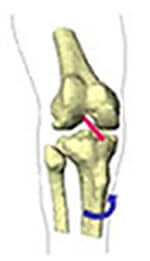

Schéma des ligaments du genou

Ligament collatéral interne (LLI)

Le ligament interne doit résister si le genou reçoit un choc de l'extérieur (valgus forcé). Il est souvent partiellement déchiré et cette lésion peut être douloureuse et gêner la rééducation.

Rupture du ligament interne

Ligament collatéral externe (LLE)

L'atteinte du ligament externe du genou survient lors d'un mécanisme de varus forcé. Elle est rare mais grave : elle s'accompagne presque toujours d'une lésion d'un ou des ligaments croisés. Sa rupture nécessite toujours une opération.

Rupture du ligament externe